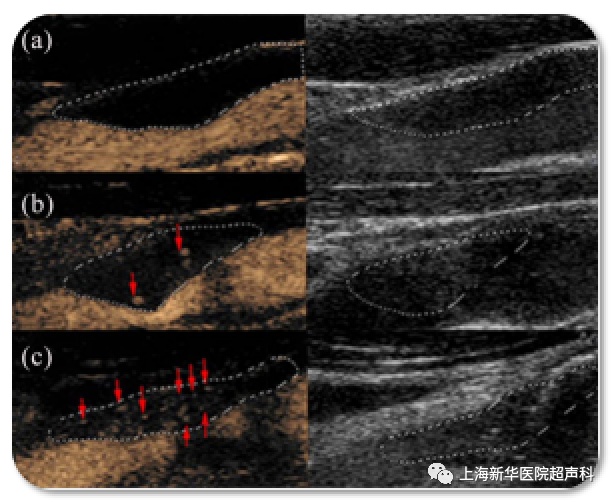

现在,我们大多将斑块分为“易损斑块”和“稳定斑块”,可以用一种新技术来评估斑块的易损性——超声造影检查,它是在常规超声检查的基础上,通过静脉注射一种微泡造影剂,可以直观的观察斑块内部的新生血管生长情况。

斑块内新生血管形成是斑块易损性的重要特征,新生血管破裂导致斑块内出血,造成斑块破裂,因此超声造影是一种早期诊断颈动脉易损斑块的安全、有效、无创的检查方法,对于指导临床治疗具有重要意义。

图1 a: 0级斑块内无微泡; b:1级斑块肩部和/或外膜见少量微泡; c: 2级斑块内见丰富微泡